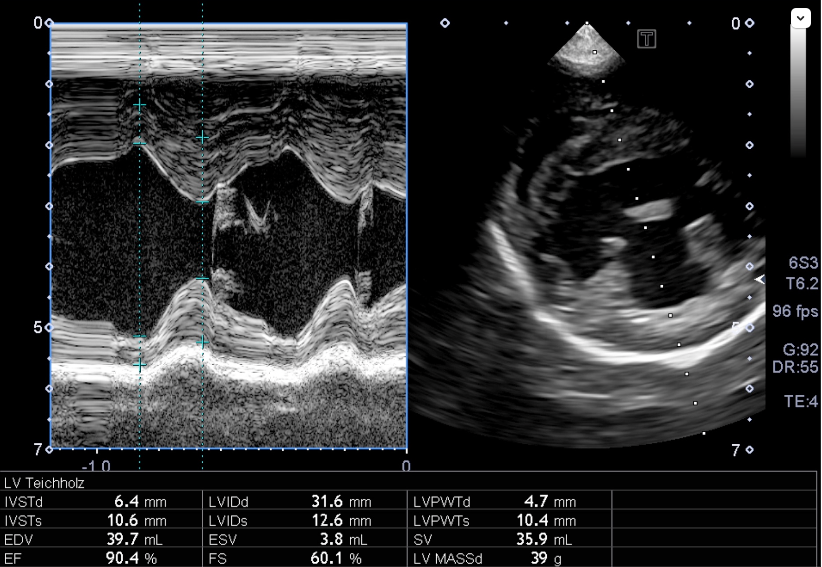

心臓エコー内服開始0日目

心臓エコー内服開始3年目 フロセミド開始

心臓エコー内服開始6年目